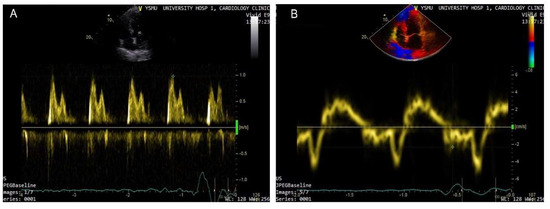

3. Speckle Tracking

4. Lung Ultrasound